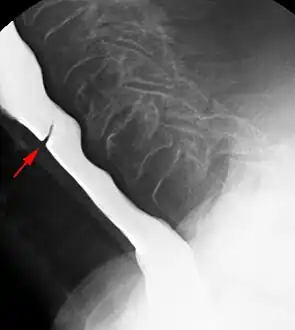

Esophageal web stenosis in barium swallow examination lateral view.

Esophageal webs are thin 2–3 mm (0.08–0.12 in) membranes of normal esophageal tissue consisting of mucosa and submucosa that can partially protrude/obstruct the esophagus. They can be congenital or acquired. Congenital webs commonly appear in the middle and inferior third of the esophagus, and they are more likely to be circumferential with a central or eccentric orifice. Acquired webs are much more common than congenital webs and typically appear in the cervical area (postcricoid).

The diagnostic test of choice is a barium swallow.